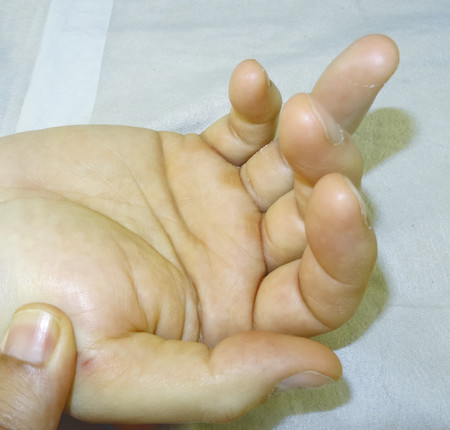

Closed rupture of extensor pollicis longus (EPL) at the wrist is the most common attrition tendon rupture. There is normally a history of distal radius fracture, often relatively undisplaced, and sometimes decades earlier. Direct repair is not possible and an extensor indicis proprius (EIP) to EPL transfer is an effective treatment.

The patient shown in Fig. 9‑1 presented to the hand trauma clinic with an inability to extend the thumb. She had been managed conservatively in cast for 8 weeks for a distal radius fracture (Fig. 9‑2). Clinical examination confirmed a ruptured EPL tendon. An EIP to EPL transfer was performed under regional anesthetic (Fig. 9‑3, Fig. 9‑4, Fig. 9‑5, Fig. 9‑6, Fig. 9‑7). The EPL which lies in the third extensor compartment is thought to undergo ischemia due to edema which consequently results in tendon necrosis and rupture.